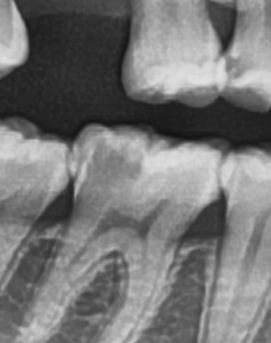

좀더 자세히 원인과 증상에 대해 살펴보면 어금니 뒤쪽은 치아 구조상 칫솔이 잘 닿지 않는 부위라서 음식물 찌꺼기가 남아 있거나 플라그가 쉽게 쌓이게 되는데 치아 사이 공간이 좁고 잇몸이 연약한 부분이라서 세균이 번식하기 쉬운 환경이 만들어지고, 이로 인해 잇몸이 붓거나 염증이 생길 가능성이 커질 수 있었어요

처음에는 가볍게 붓고 불편한 정도지만, 점점 심해지면 통증이 발생하거나, 잇몸이 붉어지고 단단해지면서 눌렀을 때 고름이 나오는 경우도 있어요. 이런 경우 단순한 염증이 아니라 치주염으로 발전할 가능성이 있기 때문에 치과에서 정확한 검진을 받는 것이 필요한 거예요

가장 주의해야 하는 문제 중에 치주염이 진행되면 어금니 뒤쪽뿐만 아니라 전체적인 잇몸이 약해질 수 있어요. 치주염은 치아를 둘러싸고 있는 조직이 손상되는 질환인데 특히 잇몸이 자주 붓거나 피가 나는 경우에는 치주염이 진행되고 있는 신호일 수 있기 때문에 단순한 잇몸 붓기로 넘기지 않는 것이 좋으며 치료를 받지 않으면 결국 치아를 지탱하는 뼈가 약해지고, 심한 경우에는 치아가 흔들리거나 빠질 수도 있었어요.